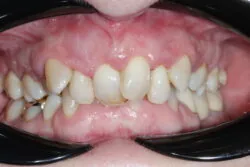

Presenting condition

A comprehensive periodontal examination revealed widespread pocketing and clinical signs of mobility in the anterior region. The upper central and lateral incisors were the most severely affected, and they showed persistent instability despite improvements elsewhere. Generalised recession and attachment loss were confirmed, with periodontal charting from September 2023 and follow-up data in November 2023 demonstrating the extent of disease and its subsequent management.

Pre-treatment images